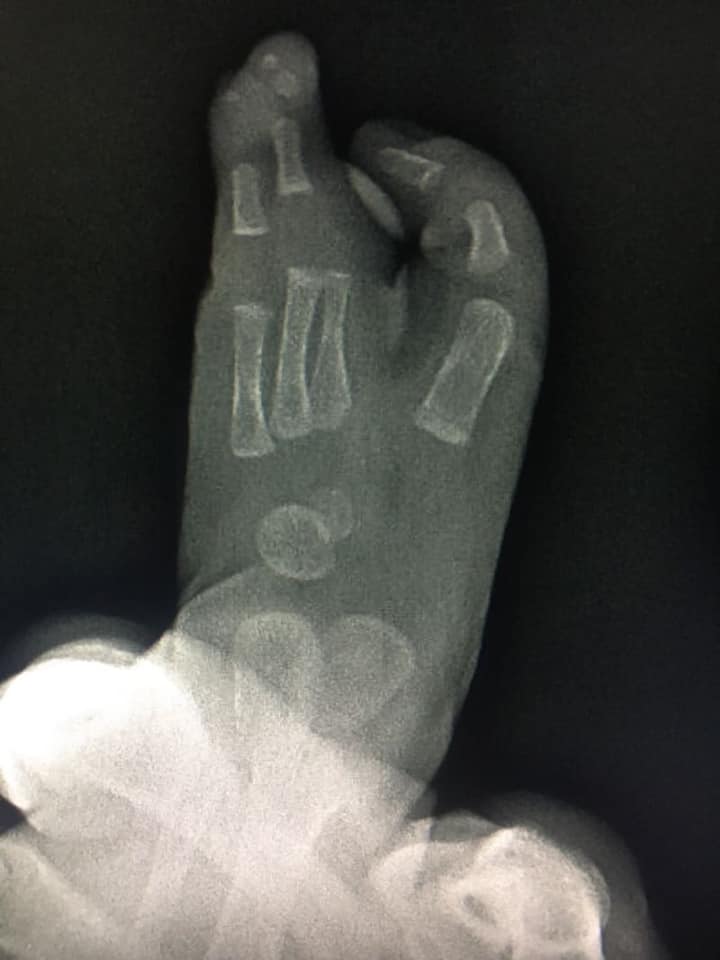

ectrodactilia deformidad en pie

Comparto el caso de mi pacientito Damián, quien me visitó por una deformidad en su pie llamada #ectrodactilia. Tuve la oportunidad de conocer su diagnóstico antes de que naciera, y a los 9 meses le realicé una cirugía de reconstrucción para la alineación del primer dedo, cierre del espacio y alineación del cuarto y quinto dedo. Aprovecho para felicitar a Damián, que hoy cumple 1 año y comienza a caminar sin dolor.